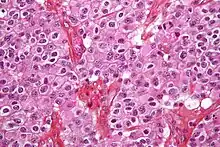

| Micrograph of an oligodendroglioma showing the characteristic branching, small, chicken wire-like blood vessels and fried egg-like cells, with clear cytoplasm and well-defined cell borders. H&E stain. | |

Oligodendrogliomas cannot currently be differentiated from other brain lesions solely by their clinical or radiographic appearance. As such, a brain biopsy is the only method of definitive diagnosis. Oligodendrogliomas recapitulate the appearance of the normal resident oligodendroglia of the brain. (Their name derives from the Greek roots 'oligo' meaning "few" and 'dendro' meaning "trees".) They are generally composed of cells with small to slightly enlarged round nuclei with dark, compact nuclei and a small amount of eosinophilic cytoplasm. They are often referred to as "fried egg" cells due to their histologic appearance. They appear as a monotonous population of mildly enlarged round cells infiltrating normal brain parenchyma and producing vague nodules. Although the tumor may appear to be vaguely circumscribed, it is by definition a diffusely infiltrating tumor.[6]

Classically they tend to have a vasculature of finely branching capillaries that may take on a "chicken wire" appearance. When invading grey matter structures such as cortex, the neoplastic oligodendrocytes tend to cluster around neurons exhibiting a phenomenon referred to as "perineuronal satellitosis". Oligodendrogliomas may invade preferentially around vessels or under the pial surface of the brain.[6]